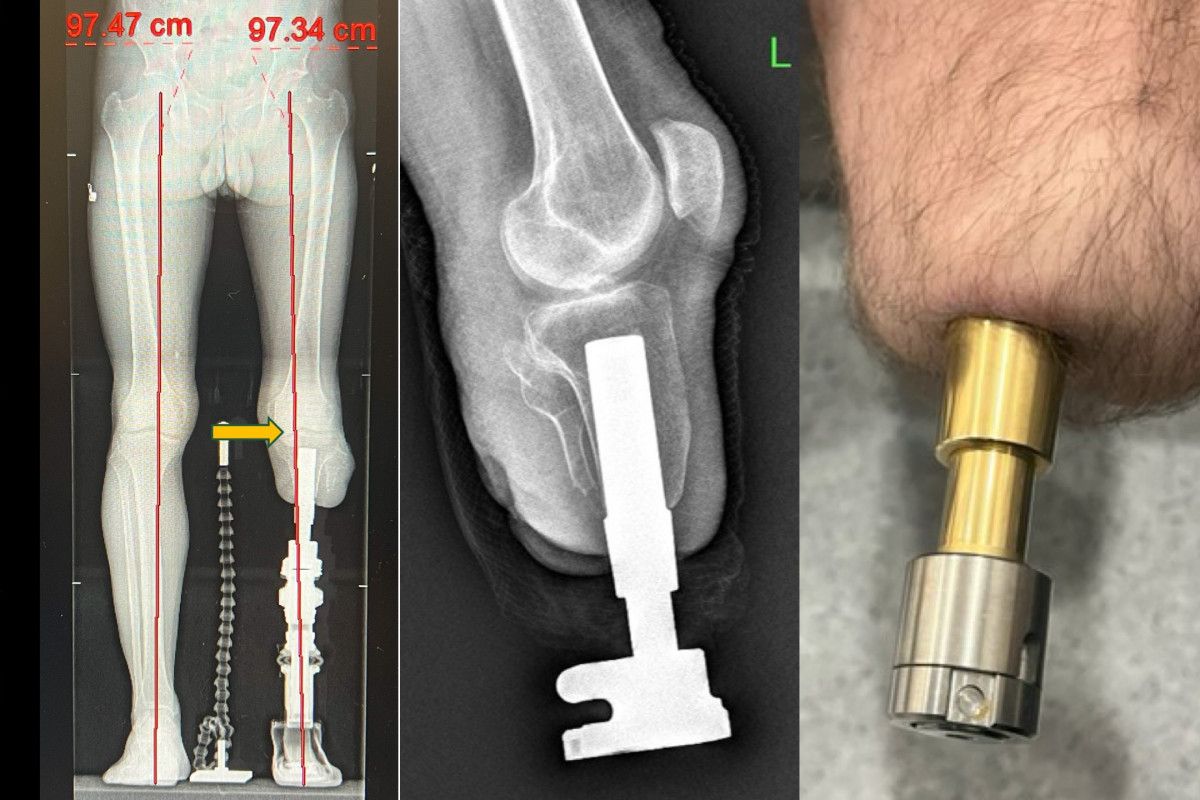

Klasik soket protezlerin yol açtığı ağrı, yara ve yürüme zorluklarına bir alternatif sunan osseointegrasyon prosedürü, amputasyon hastalarına umut veriyor.

Kemiğe yerleştirilen implantlarla daha doğal ve konforlu bir yürüyüş sunan bu prosedür Türkiye’de de uygulanıyor.

Bu metotta, kemiğe yerleştirilen implant sayesinde yük direkt kemiğe aktarıldığından, çok daha doğal ve konforlu bir yürüyüş mümkün oluyor.

Osseointegrasyon protezlerinin yapıldığı uzuvlar hakkında da bilgi veren Prof. Dr. Kara, yöntemin uyluk, kaval kemiği, dizüstü ve dizaltı üzere bölgelerin yanı sıra üst kol amputasyonlarında da muvaffakiyetle uygulandığını aktardı.